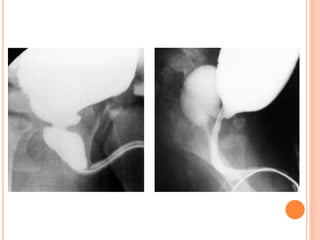

VOIDING

CYSTOURETHROGRAPHY

VCUG is commonly performed in children

with prenatally diagnosed hydronephrosis,

urinary tract infections, and voiding

abnormalities.

The procedure should include assessment

of the spine and pelvis; masses or opaque

calculi; bladder capacity, contour, and

emptying capability; presence and grade of

reflux; and urethral appearance.

IMAGING DURING VOIDING

Bladder capacity={Age(ys)+2}x30.

VCUG is commonlyperformed in children with prenatally diagnosed hydronephrosis, urinary tract infections, and voiding abnormalities. The procedure should include assessment of the spine and pelvis; masses or opaque calculi; bladder capacity, contour, and emptying capability; presence and grade of reflux; and urethral appearance.

INTERMEDIATE FILLING Vesicoureteral refluxcan be seen on oblique radiographs obtained just before voiding and can be graded after voiding with the International Reflux System.

IMAGING DURING VOIDING Bladdercapacity={Age(ys)+2}x30. A smaller than expected voiding volume may also indicate a neurologic abnormality (spastic bladder) or active bladder infection.